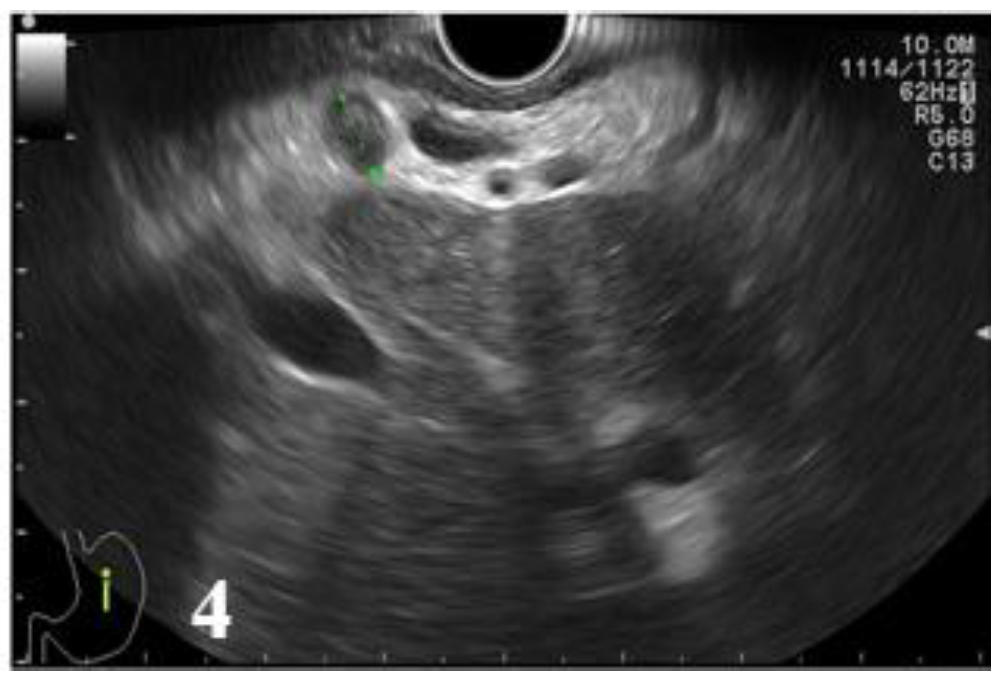

Figure 1.

Postcontrast CT, arterial phase, sagittal plane. Circumferential marked parietal thickening of the distal thoracic esophagus and gastroesophageal junction with heterogeneous structure that generates stenosis.